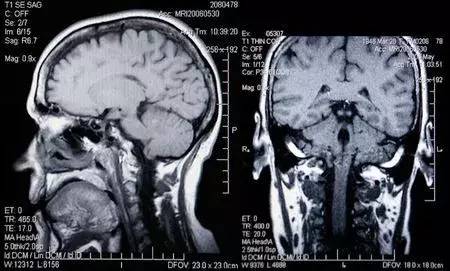

3、核磁共振(MRI): 中文全稱磁共振成像,利用原子核自旋運動的特點,在外加磁場內,經射頻脈沖激后產生信號,用探測器檢測并輸入計算機,并轉換成圖像。

2、頸椎腰椎——最佳選核磁、次選CT

一般對于脊柱的疾病,我們首先進行X光片的檢查,畢竟X光片造價比較低。但是如果我們想看看自己有沒有椎間盤突出,是否壓迫到了神經,那最好的方式就是拍個核磁。因為間盤、神經都屬于軟性的組織,核磁看的最清楚。但是如果是想看看有沒有椎體滑脫還是應該拍X光片。如果懷疑有脊柱腫瘤、結核,那最好的方式就是拍CT。 “